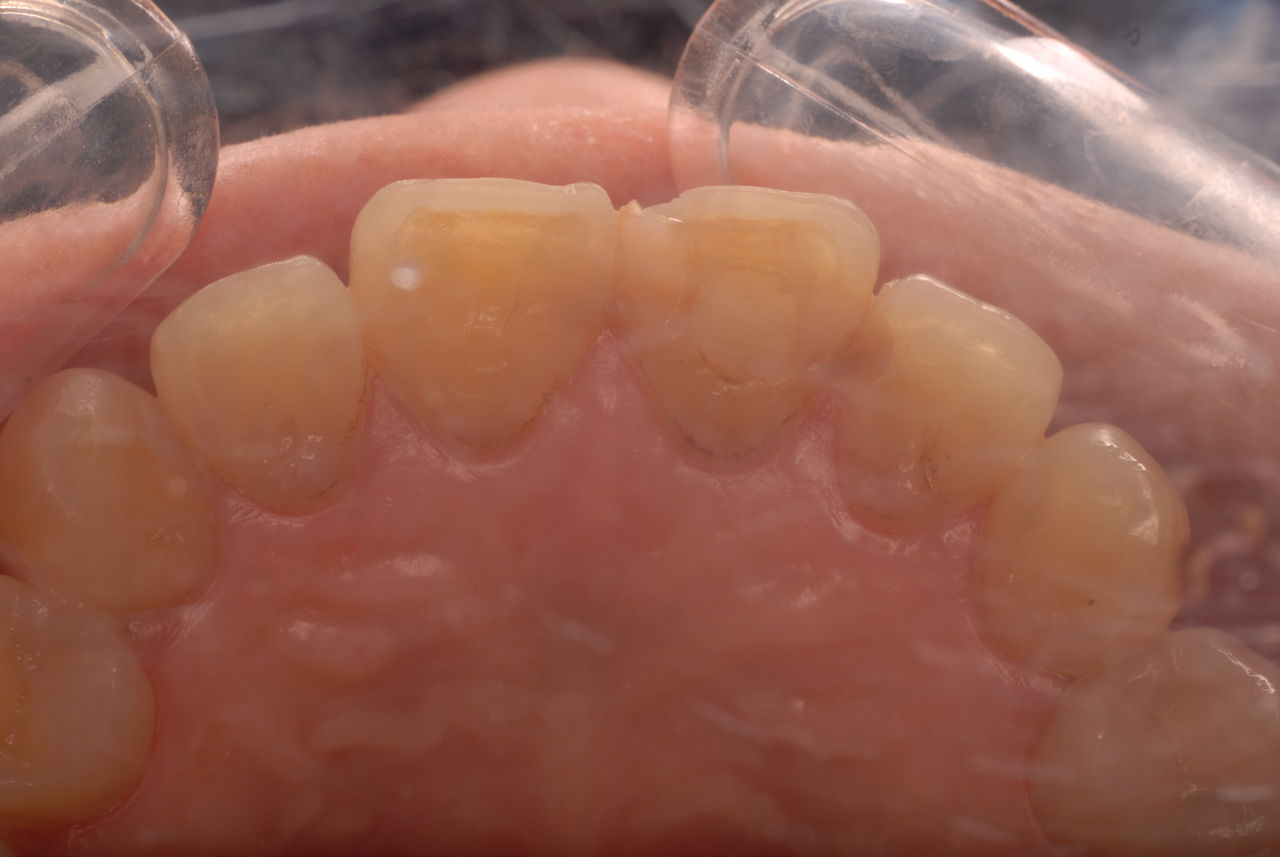

殆ど出っ張りがない上顎の部分です。

歯周病になっていましたが、少し色が黄色くなっているだけで比較的綺麗な歯の状態です。

平成9年来院神経を取り、同時に歯周病の話をしてそのまま来なくなっていたかたですが、たまたま一部欠けてきました。それで来院。